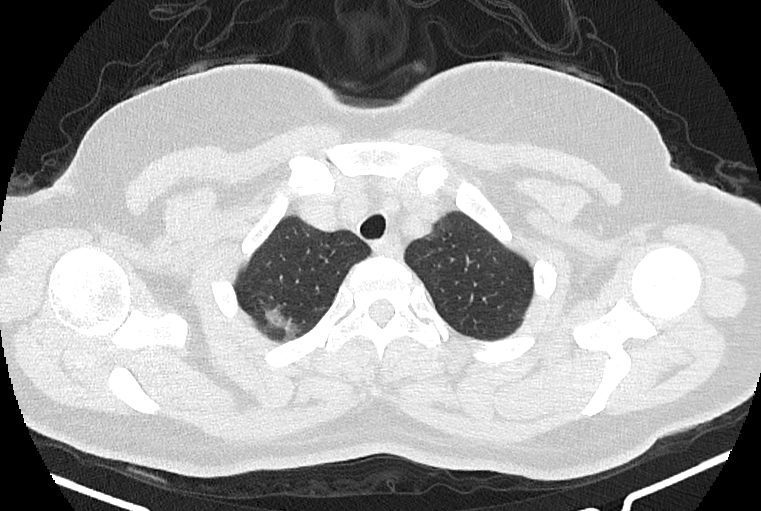

در HRCT از ريه ها(اسپيرال ، مولتي ديتکتور 16، مقاطع اگزيال با ضخامت 1mm بدون فاصله ) ، بدون كنتراست تزريقي :

-Ground glass opacities Patchy پراکنده در ريه ها مشهود است که مطرح کننده Viral pneumonia مي باشد . ( با درگيري 20 درصد حجم ريه )

-کلسیفیکاسیون دیواره آئورت و عروق کرونر ، تغییرات DJD در ستون فقرات ونشانه های CABG مشهود است .

نتیجه : Highly suggestive of COVID-19